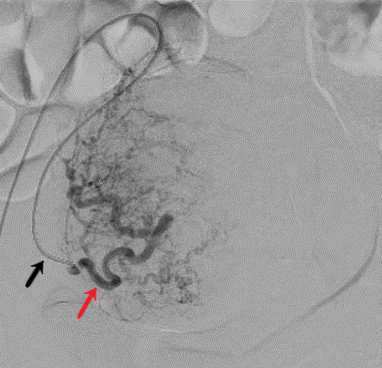

Image d'artériographie d'une procédure d'embolisation utérine du côté droit et gauche chez une même patiente.

Les formations tubulées noires correspondants aux artères et vaisseaux sanguins telles que visualisées par le radiologue interventionnel lors de l'injection de produit de contraste.

On individualise successivement le cathéter permettant l'injection du produit (flèche noire), l'artère utérine (flèche rouge) avec visualisation d'un des fibromes utérines à traiter chez cette patiente (flèche orange) sous forme d'un réseau artériel en arc de cercle.